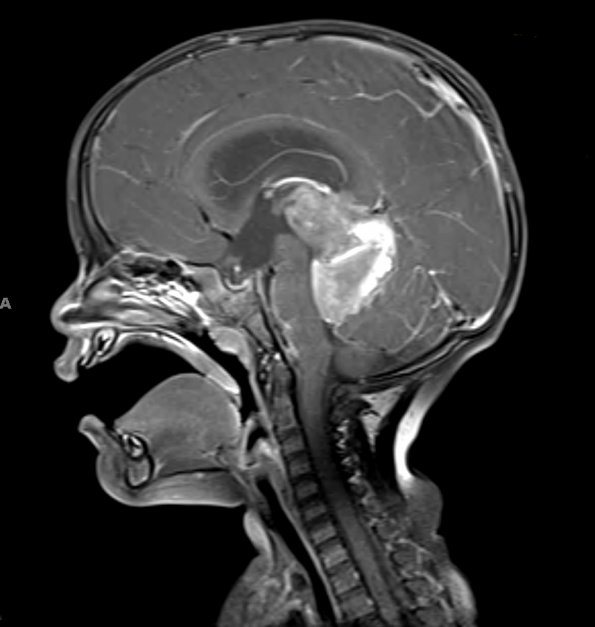

17A2 ATRT (Case 17) T1 W 1 - Copy

The mass enhances with contrast administration in this T1-weighted scan.